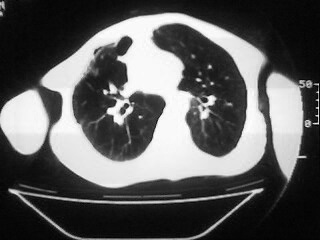

m,45,咳嗽、气憋月余。先天性畸形

1)两肺上叶继发性肺结核,部分肺间质纤维化。2)慢性支气管炎。3)肺气肿,两上肺多发性肺大泡。4)右侧胸膜增厚可能。5)脊柱上胸段畸形。

肺间质纤维化、肺大泡

两上肺结核、纤维化,两上肺肺大泡,

考虑:1)两肺上叶继发性肺结核,部分肺间质纤维化。2)慢支肺气肿并两上肺多发性肺大泡。3)右侧胸膜增厚可能。5)脊柱上胸段畸形。

补充一下,病人有强直性脊柱炎十多年